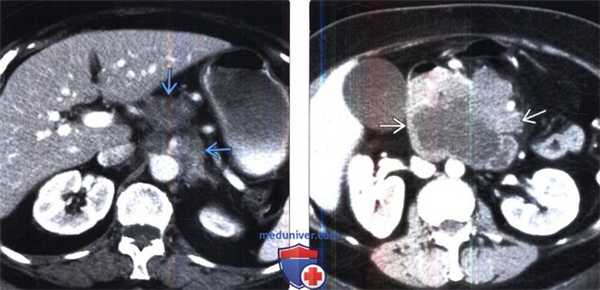

(Слева) КТ с контрастированием, аксиальная проекция: слившаяся околочревная лимфаденопатия вследствие НХЛ.

(Справа) КТ с контрастированием, аксиальная проекция: визуализирована панкреатическая НХЛ в виде массивного образования в области головки поджелудочной железы. Лимфома расположена в перипанкреатической группе лимфатических узлов, однако внешне может имитировать первичную опухоль поджелудочной железы.